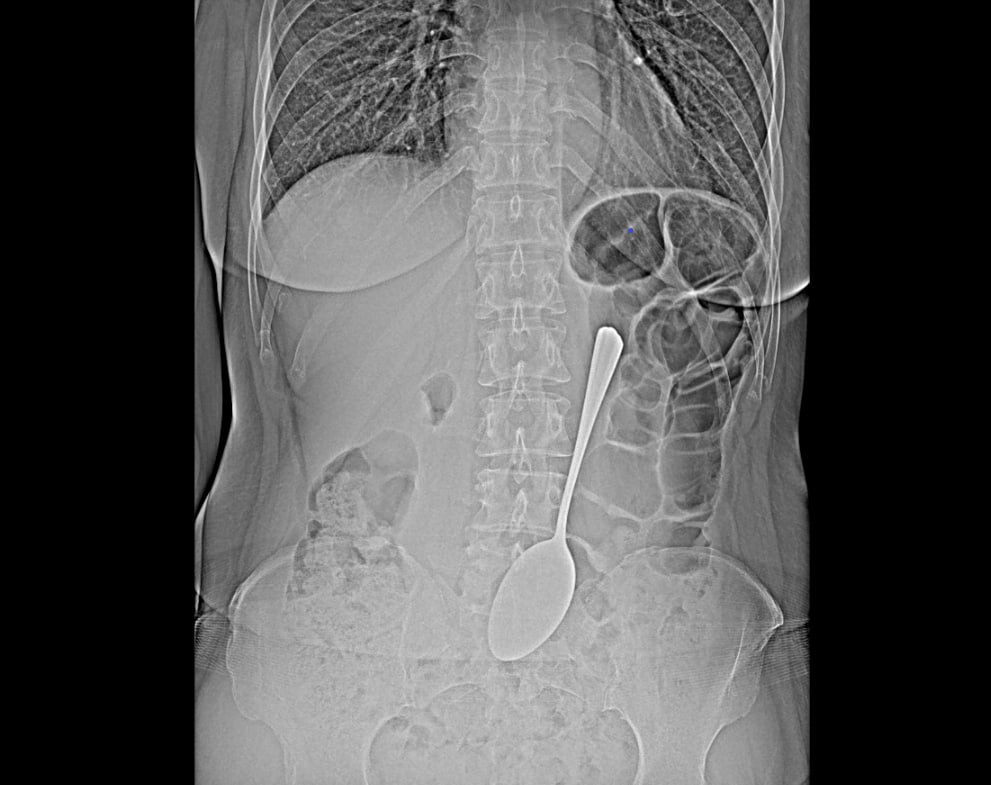

В Улан-Удэ врачи спасли пациентку, проглотившую столовую ложку

Женщина не дала объяснений своему поступку